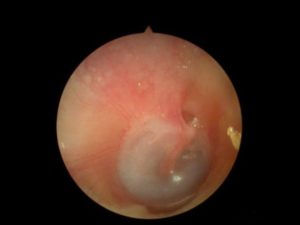

- Микроскопия. Это обследование назначют для того, чтобы дифференцировать дефекты барабанной перепонки и заболевание наружного уха.

В ходе диагностических исследований отоларингологу необходимо исключить наличие других заболеваний, сопровождающихся понижением слуха (болезни Меньера, отита, отосклероза, инородного тела уха, лабиринтита).

Электрокохлеография дает возможность дифференцировать кохлеарный неврит от болезни Меньера. Для исключения заболеваний наружного уха и изменений со стороны барабанной перепонки проводится отоскопия и микроотоскопия.